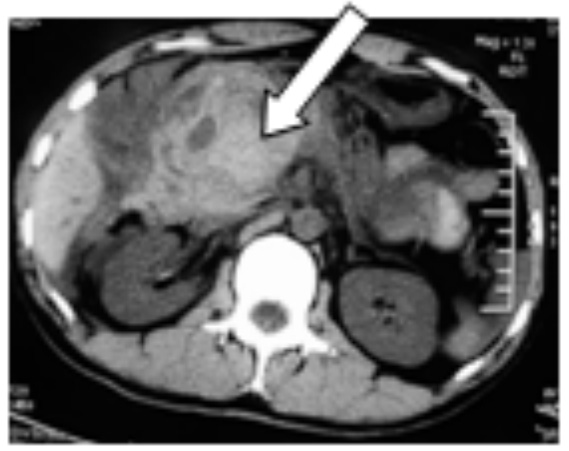

图 2 穿刺引出脓性积液